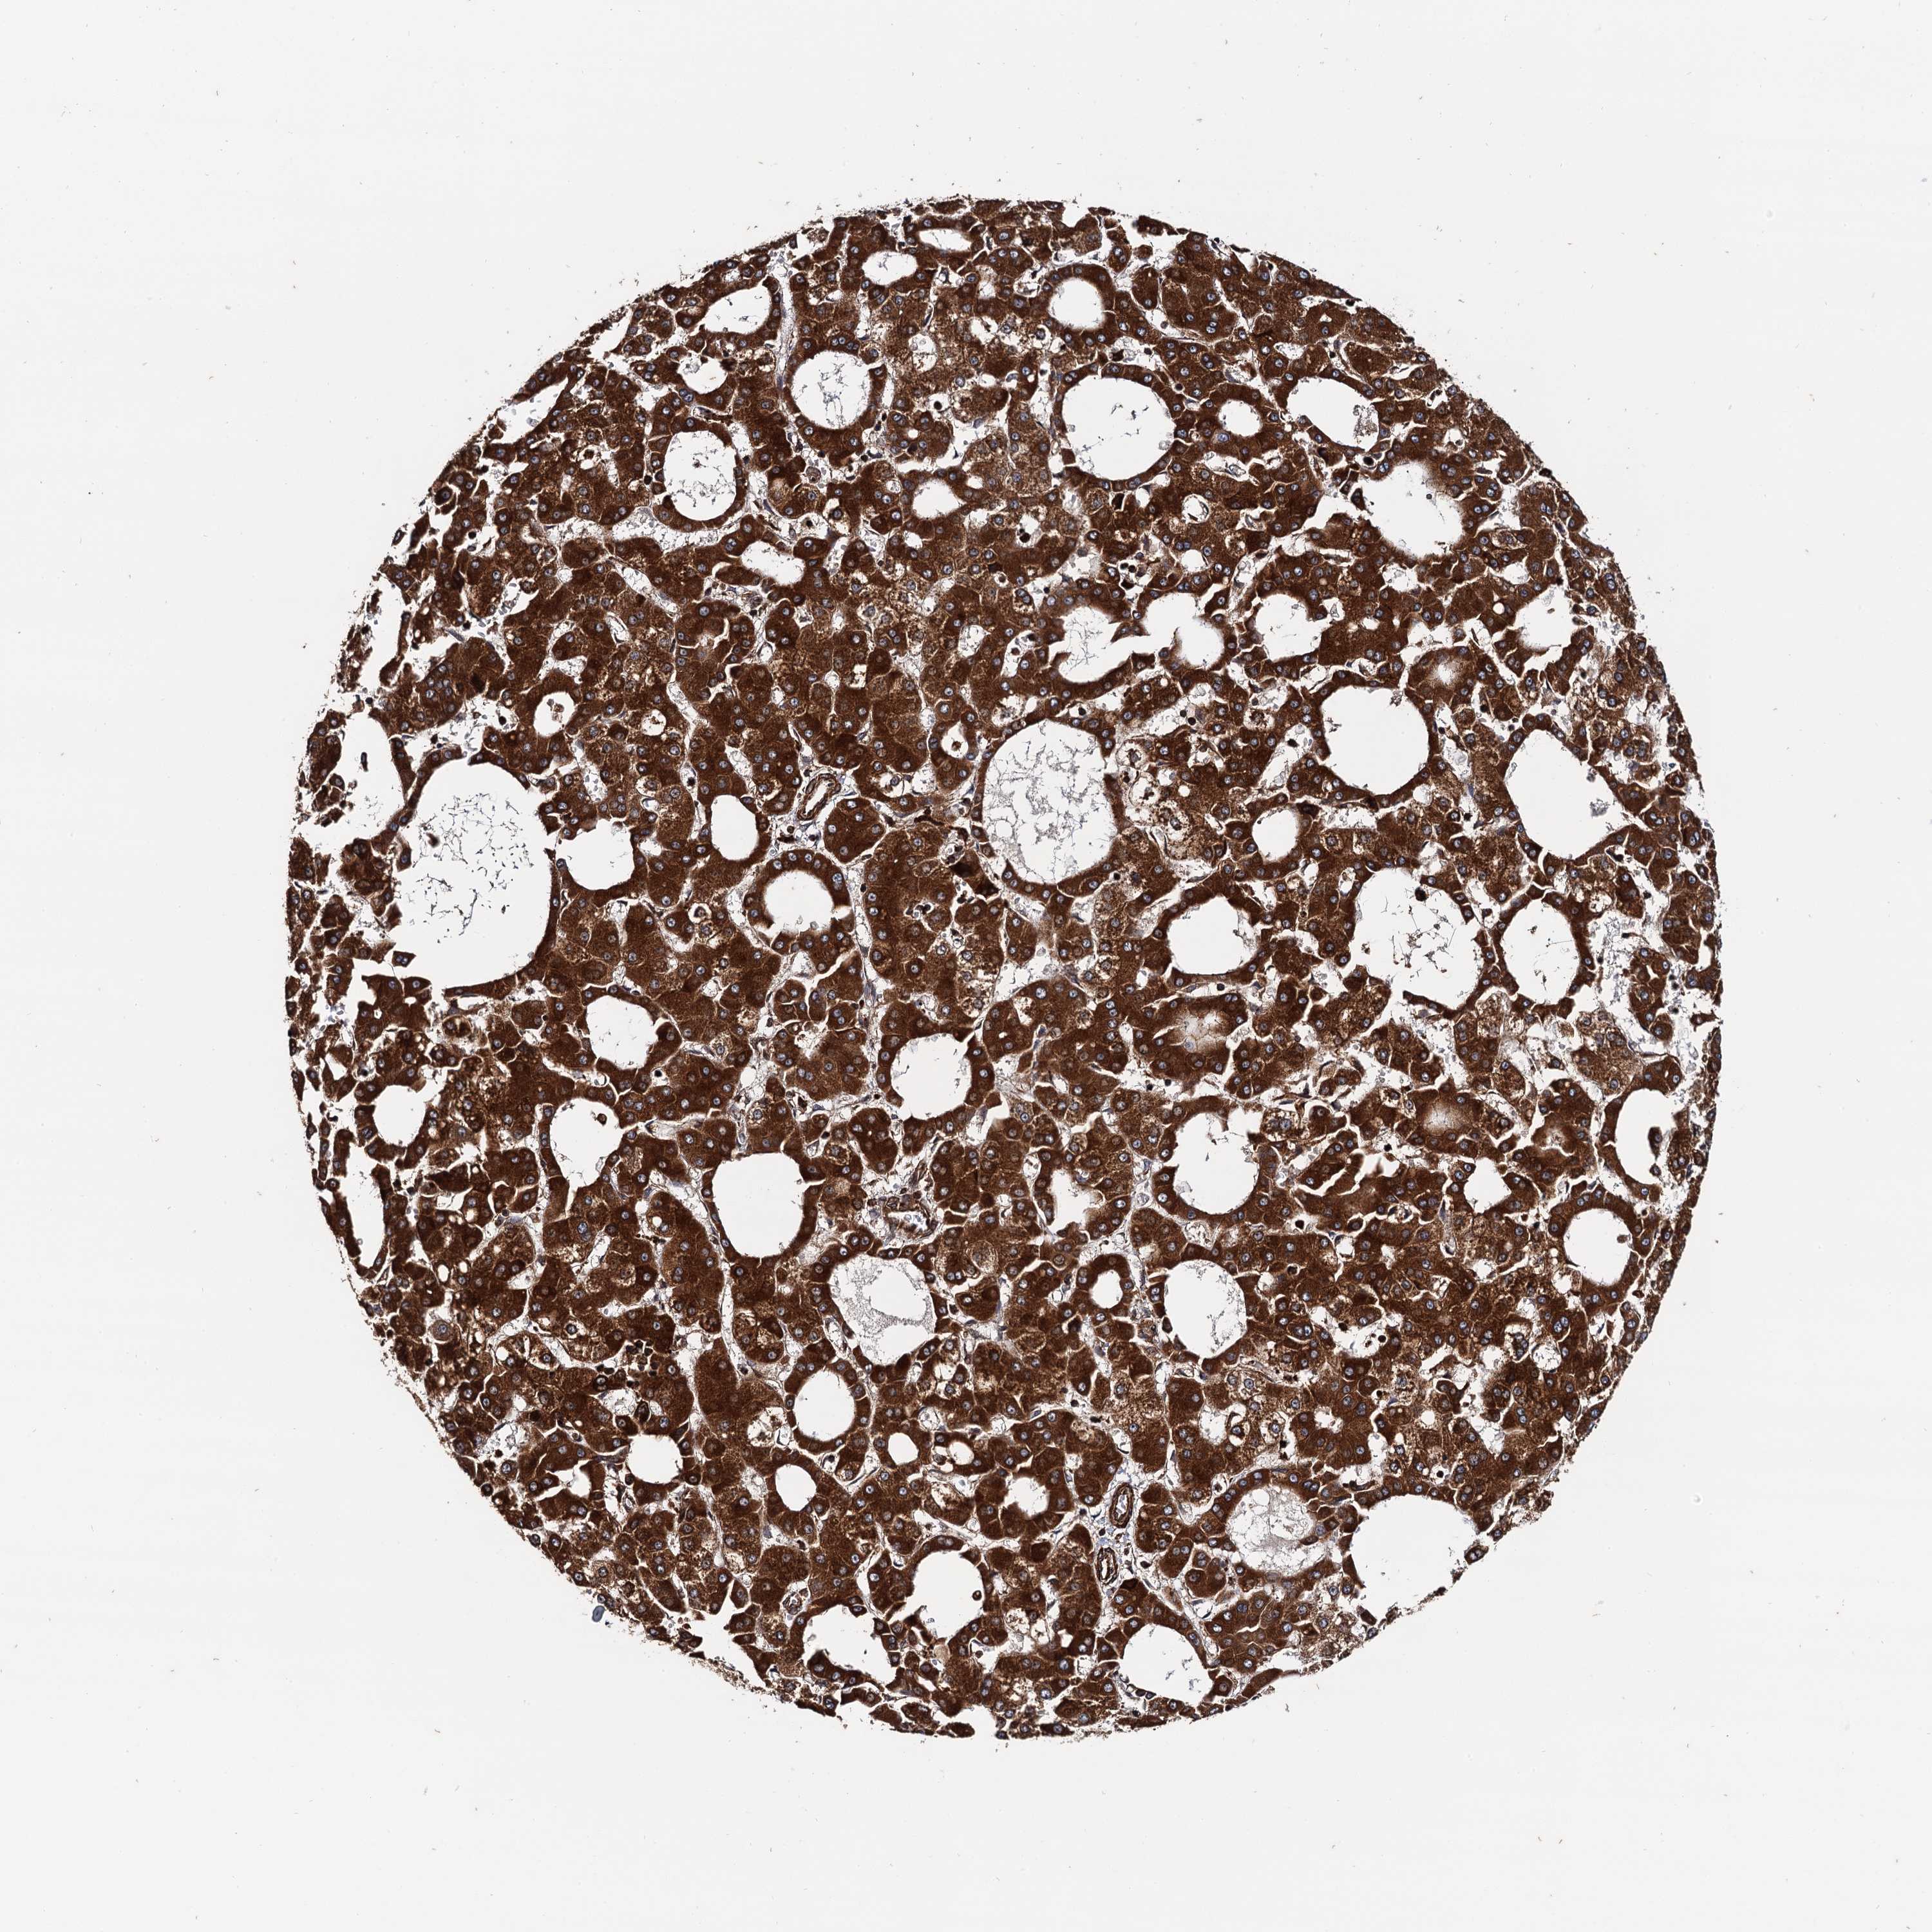

LIVER CANCER - Protein expressioni

A mouse-over function shows sample information and annotation data. Click on an image to view it in a full screen mode. Samples can be filtered based on level of antibody staining by selecting one or several of the following categories: high, medium, low and not detected. The assay and annotation is described here.

Note that samples used for immunohistochemistry by the Human Protein Atlas do not correspond to samples in the TCGA dataset.

Antibody stainingi

Antibody staining in the annotated cell types in the current human tissue is reported as not detected, low, medium, or high, based on conventional immunohistochemistry profiling in selected tissues. This score is based on the combination of the staining intensity and fraction of stained cells.

Each image is clickable and will lead to virtual microscopy that enables deeper exploration of all samples and also displays staining intensity scores, fraction scores and subcellular localization as well as patient and tissue information for each sample.

Antibody HPA040866

Staining

High

Medium

Low

Not detected

Intensity

Strong

Moderate

Weak

Negative

Quantity

>75%

75%-25%

<25%

None

Location

Nuclear

Cytoplasmic/membranous

Cytoplasmic/membranous,nuclear

Cholangiocarcinoma

Carcinoma, Hepatocellular, NOS